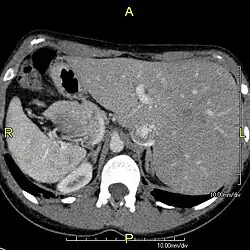

Diagnosis of situs inversus can be made using imaging techniques such as x-ray, ultrasound, CT scan, and magnetic resonance imaging (MRI).[9]

The condition affects all major structures within the thorax and abdomen. Generally, the organs are simply transposed through the sagittal plane. The heart is located on the right side of the thorax, the stomach and spleen on the right side of the abdomen and the liver and gall bladder on the left side. The heart's normal right atrium occurs on the left, and the left atrium is on the right. The lung anatomy is reversed and the left lung has three lobes while the right lung has two lobes. The intestines and other internal structures are also reversed from the normal, and the blood vessels, nerves, and lymphatics are also transposed.

In rarer cases such as situs ambiguus or heterotaxy, situs cannot be determined. In these patients, the liver may be midline, the spleen absent or multiple, and the bowel malrotated. Often, structures are duplicated or absent altogether. This is more likely to cause medical problems than situs inversus totalis.[2]